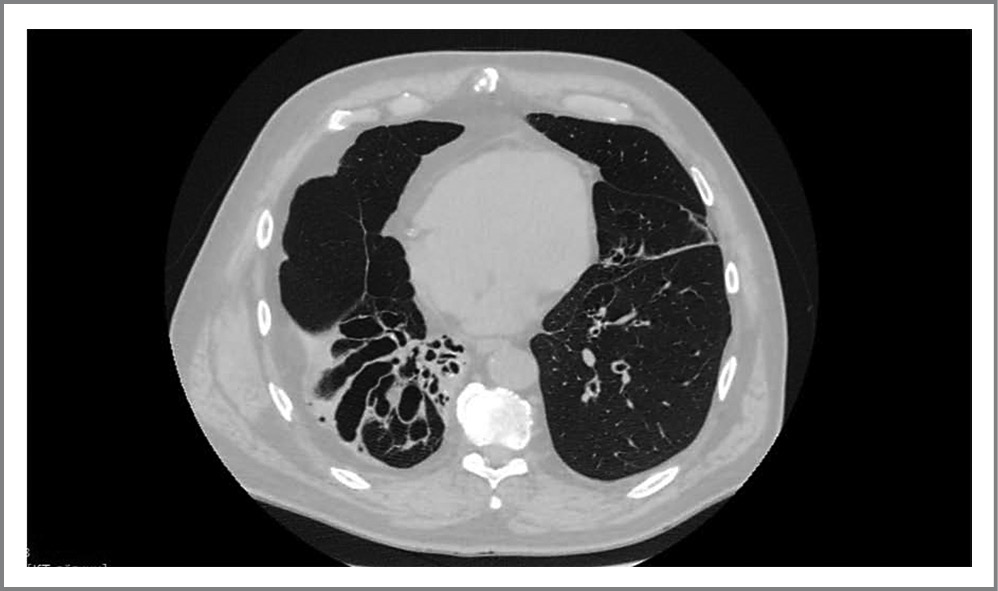

Клинические проявления врожденной гипоплазии легочной ткани

В клинике наблюдается мужчина 75 лет, который с раннего детства страдал частыми инфекционными заболеваниями дыхательных путей; каждое обострение сопровождалось усилением кашля, увеличивалось отхождение слизисто-гнойной мокроты и усиливалась одышка. Более 30 лет назад пациент прошел обследование в клинике. При проведении компьютерной томографии (КТ) органов грудной клетки обнаружена гипоплазия нижней доли правого легкого, кистозная дегенерация бронхов, адгезивный плеврит.

Рис. 4. КТ больного с врожденной гипоплазией легочной ткани.

Fig. 4. CT scan of a patient with congenital hypoplasia of pulmonary tissue.

На рис. 4 представлены данные КТ наблюдаемого больного. В мокроте постоянно высевалась Pseudomonas aeruginosa. Многократно проводили антибактериальную терапию, к которой возбудитель заболевания – синегнойная палочка – стал резистентен. В программу лечения пациента включены бактериофаги, и в лабораторных условиях приготовлена индивидуально вакцина против P. aeruginosa. В конечном счете инфекционный процесс удалось стабилизировать и минимизировать число обострений инфекционных заболеваний исследуемого лица. Однако возникает вопрос о природе рецидивирующей инфекции дыхательных путей данного больного. В этом случае речь идет о врожденных гипоплазии нижней доли правого легкого и кистозных бронхоэктазов, что следует отнести к области эмбриопатий.